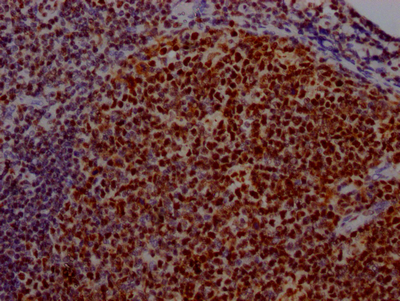

• IHC image of CSB-RA192026A0HU diluted at 1:100 and staining in paraffin-embedded human tonsil tissue performed on a Leica BondTM system. After dewaxing and hydration, antigen retrieval was mediated by high pressure in a citrate buffer (pH 6.0). Section was blocked with 10% normal goat serum 30min at RT. Then primary antibody (1% BSA) was incubated at 4℃ overnight. The primary is detected by a Goat anti-rabbit IgG polymer labeled by HRP and visualized using 0.05% DAB.